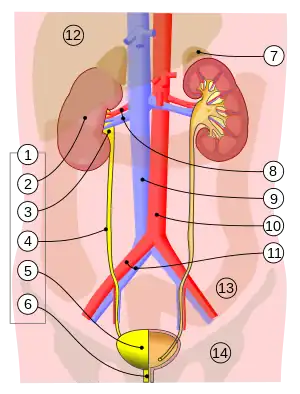

1. Human urinary system: 2. Kidney, 3. Renal pelvis, 4. Ureter, 5. Urinary bladder, 6. Urethra. (Left side with frontal section) 7. Adrenal gland Vessels: 8. Renal artery and vein, 9. Inferior vena cava, 10. Abdominal aorta, 11. Common iliac artery and vein Transparent: 12. Liver, 13. Large intestine, 14. Pelvis | |